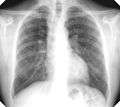

Miner's lung with silicosis and tuberculosis.

For uncomplicated silicosis, chest x-ray will confirm the presence of small (< 10 mm) nodules in the lungs, especially in the upper lung zones. Using the ILO classification system, these are of profusion 1/0 or greater and shape/size "p", "q", or "r". Lung zone involvement and profusion increases with disease progression. In advanced cases of silicosis, large opacity (> 1 cm) occurs from coalescence of small opacities, particularly in the upper lung zones. With retraction of the lung tissue, there is compensatory emphysema. Enlargement of the hilum is common with chronic and accelerated silicosis. In about 5-10% of cases, the nodes will calcify circumferentially, producing so-called "eggshell" calcification. This finding is not pathognomonic (diagnostic) of silicosis. In some cases, the pulmonary nodules may also become calcified.